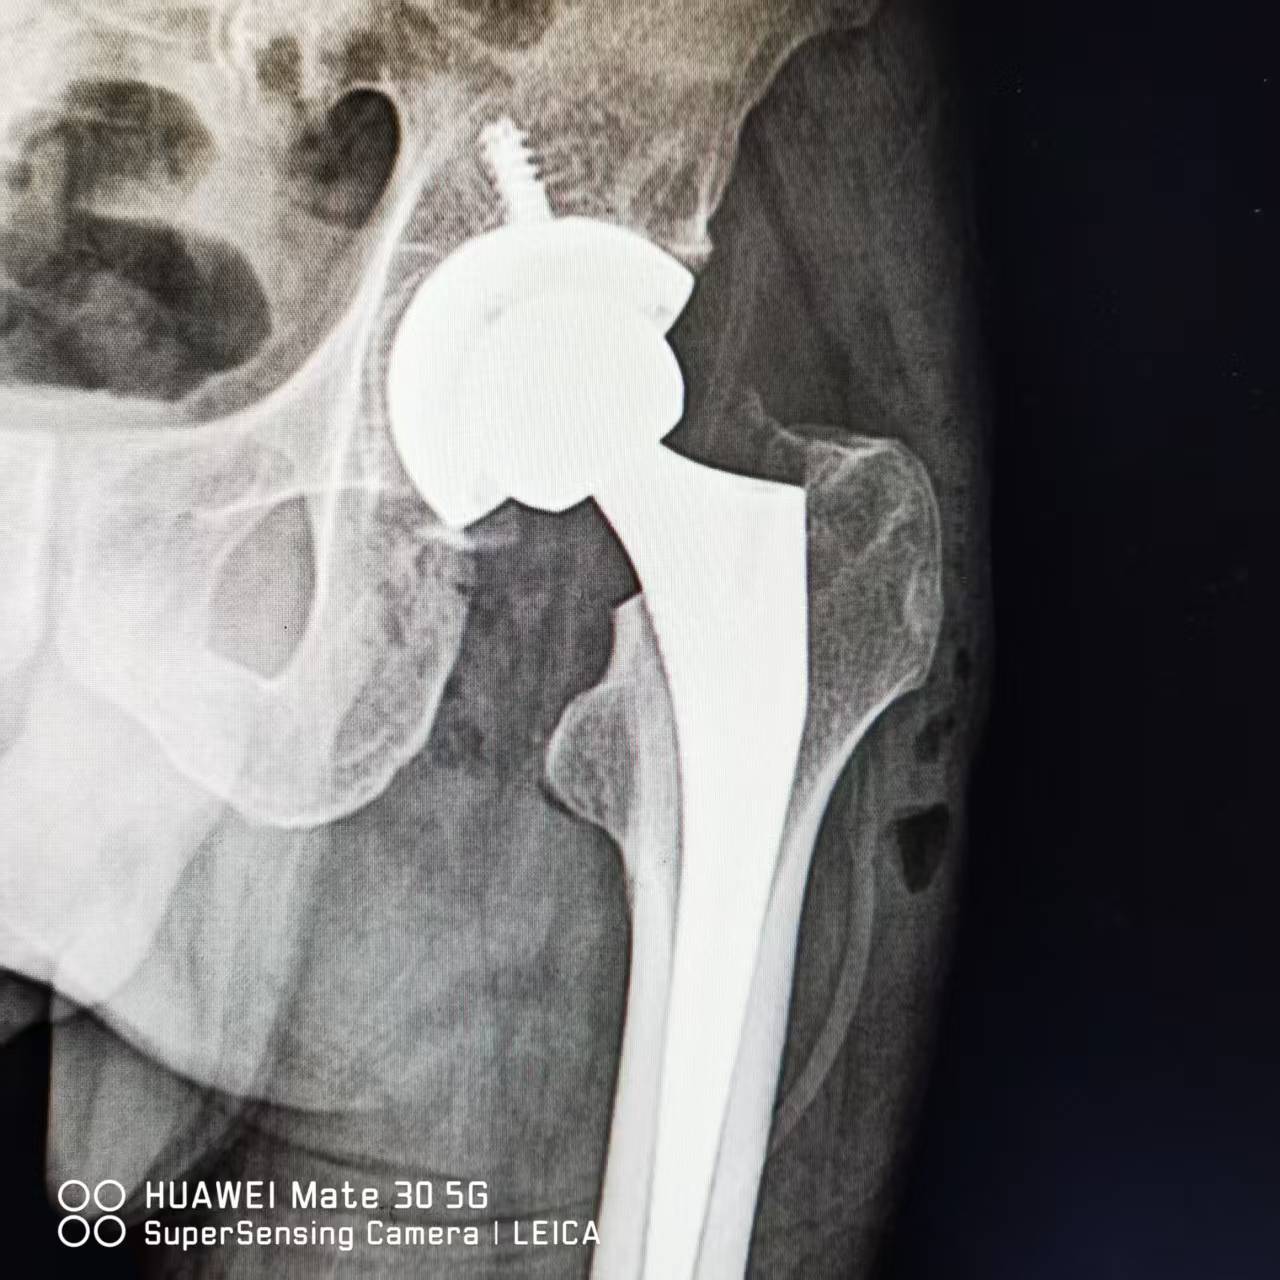

在我院骨科成功实施‌左侧全髋关节置换术‌。

术后一周恢复良好,术后第3天即能在双拐辅助下行走,目前疼痛缓解显著,关节功能逐步恢复,符合出院标准‌。